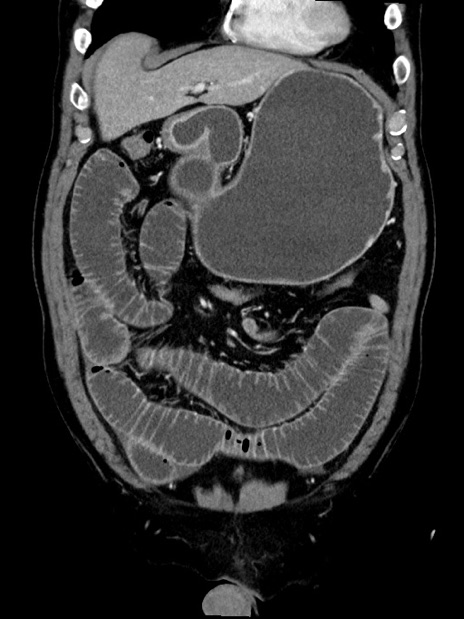

症例35(冠状断像)

【症例】70歳代 男性

【主訴】腹部膨満、嘔吐

【現病歴】昨日より腹部膨満感出現。本日増悪し、仙痛出現。嘔吐あり、受診。

【既往歴】糖尿病、胆摘後

【身体所見】BP 149/80mmHg、HR 74/min、BT 35.9℃、腹部:膨満、軟、圧痛なし。腸雑音減弱あり。上腹部正中切開瘢痕あり。

【データ】WBC 13500、CRP 1.72